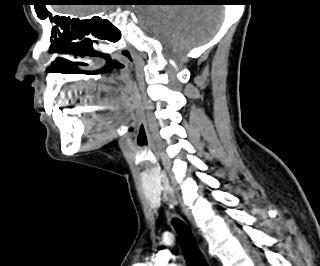

Мультиспиральная компьютерная томография – это высокоинформативный лучевой метод диагностики различной патологии мягких тканей шеи, включая воспалительные заболевания, травматические повреждения и опухолевые процессы. КТ позволяет оценить состояние щитовидной железы, паращитовидных желез, гортани, верхней части пищевода, магистральных сосудов шеи, шейных лимфоузлов и окружающих мягких тканей.

Метод КТ основан на применении рентгеновского излучения. Однако в отличие от обычного рентгена, при котором снимки производятся в одной плоскости, при КТ излучатель рентгеновских лучей постоянно двигается вокруг объекта исследования, проводя сканирование в различных плоскостях, а затем трансформируя полученные данные в цифровые трехмерные изображения. Это дает возможность визуализировать органы и ткани в мельчайших подробностях, а с помощью объемных 3D-реконструкций наглядно оценить пространственное расположение органов и патологических образований.

Рентгеновские лучи лучше всего поглощаются плотными структурами, такими как костная ткань. Поэтому кости хорошо видны на снимках КТ. Это делает компьютерную томографию незаменимой при необходимости обследования, в частности, костного скелета гортани. Однако для улучшения визуализации мягких тканей требуется введение специального контрастного препарата, поэтому КТ мягких тканей шеи проводится с контрастным усилением.

Для контрастирования используется йодсодержащее контрастное вещество, которое в составе рентгеноконтрастного препарата вводится в вену пациенту непосредственно во время исследования. Благодаря способности контраста поглощать рентгеновские лучи на снимках КТ хорошо контрастируются кровеносные сосуды и опухолевые образования, имеющие, как правило, развитую сосудистую сеть. Методика внутривенного болюсного контрастирования помогает обнаружить воспалительные изменения, отличить доброкачественные опухоли от злокачественных, выявить поражение лимфатических узлов и степень прорастания опухоли в магистральные сосуды и окружающие ткани.